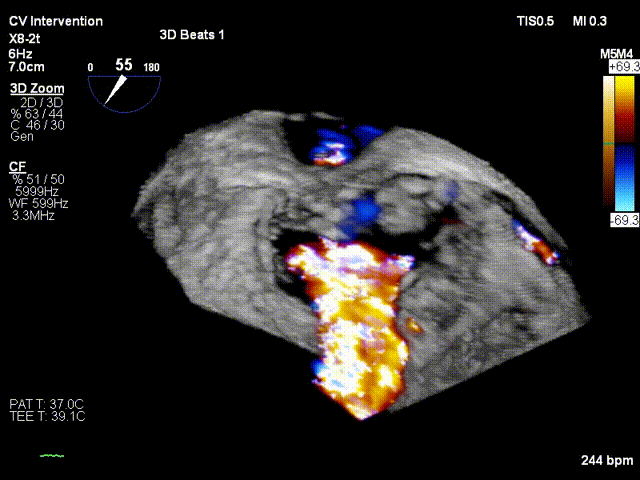

考虑患者残余反流仍偏高,经团队评估后,遂植入第二个夹子。术后即刻(植入第二个夹子)TEE示:二尖瓣反流降低至微量,二尖瓣压差1mmHg;测定左房压力:19/16/14mmHg,手术成功。患者术后即刻麻醉清醒,血压维持在110/60mmHg, 胸闷,呼吸困难症状明显缓解。

3D基线view

3D一个架子后

3D Final